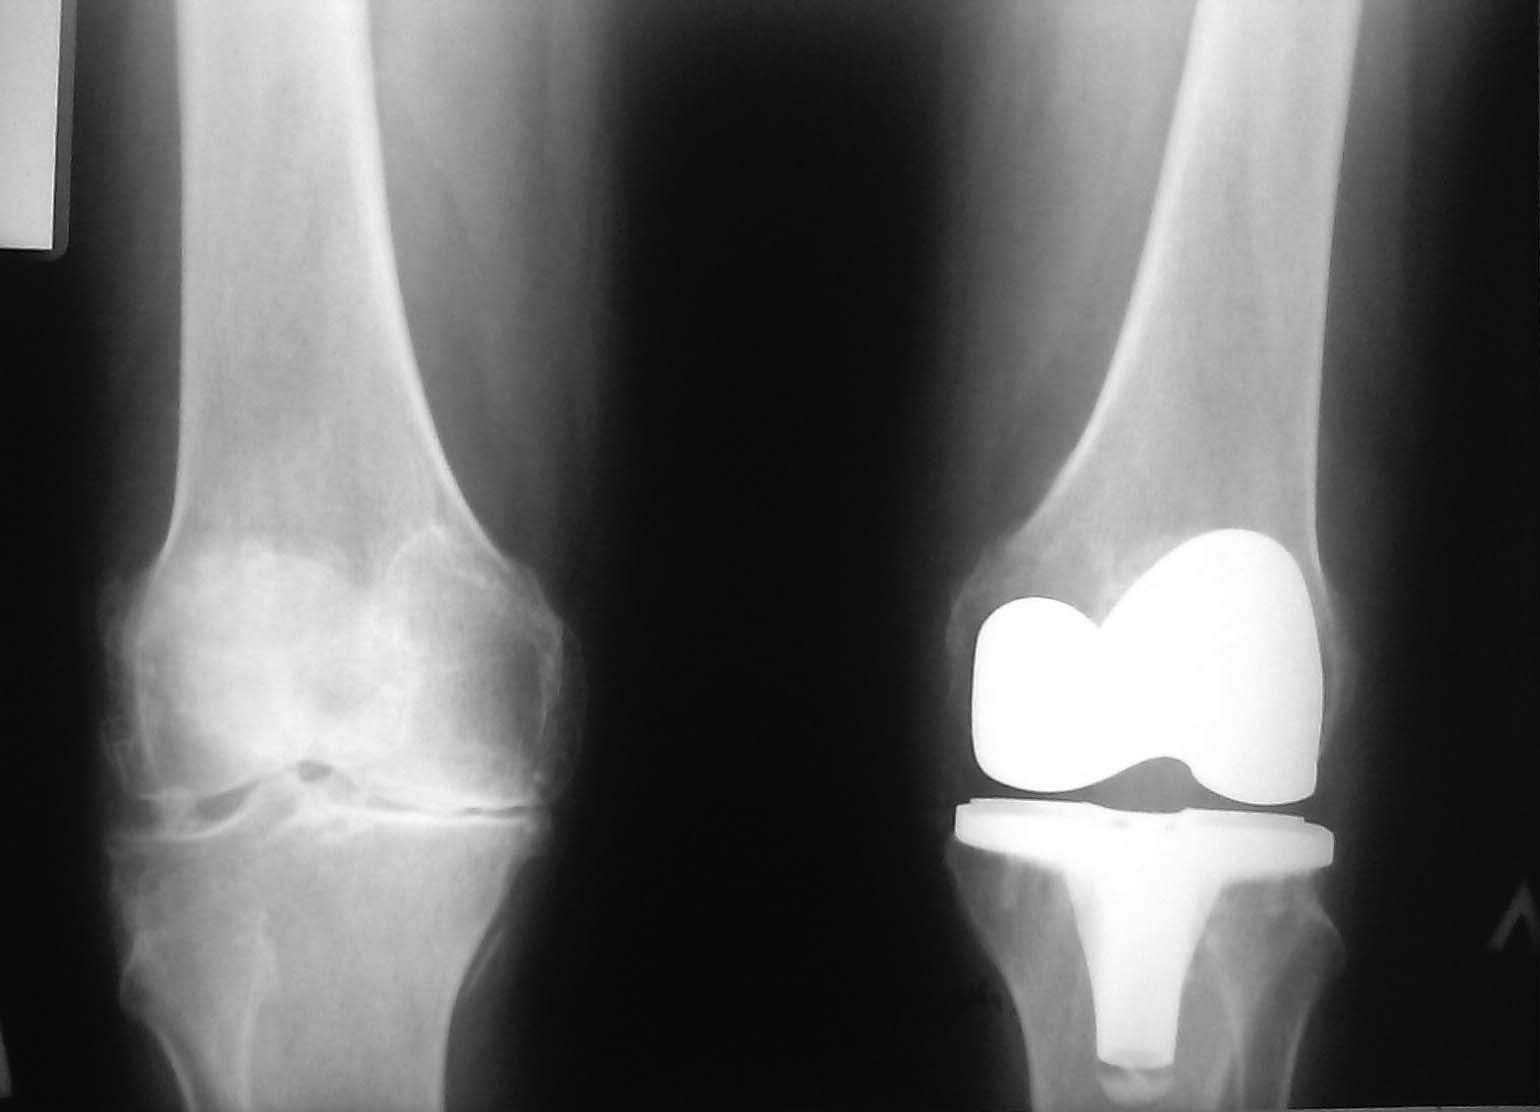

Пациентка 65лет, в течении многих лет беспокоят боли в коленных суставах. В декабре 2011г

выполнено ТЭП левого коленного сустава , послеоперационный период протекал относительно

гладко , если не считать, что в течении первых двух недель оперирующим хирургом было

выполнено 4-5 пункций сустава, с изъятием "розового" цвета жидкости (со слов). В дальнейшем

наблюдается по месту жительства, с декабря по 22.05.12г выполнено 45-50 пункций коленного

сустава с получением 40-80 мл синовиальной жидкости чаще желтого цвета, без примесей,

иногда с геморрагическим компонентом. проводились и просто пункции и периодически с

добавлением 0.5-1.0 дипроспана + в/м НПВС, сосудистые и др. За прошедшее время нам кажется

что наступает некоторое улучшение, в том что приходится пунктировать реже (1раз в 7-10 дней)

и колличество жидкости становится поменьше. Пациентка консультирована у оперир. хирурга,

бралась синовиалка на Б\х ( без особенностей). Следует отметить, что пациентку беспокоят

щелчки в суставе при ходьбе ( при сгибании-разгибании). Посдкажите в чем проблема, чем можно

помочь женщине. Представить не трудно , что у пациентки развивается невроз на фоне всего

этого. Заранее благодарен. С уважением Роман.Д.